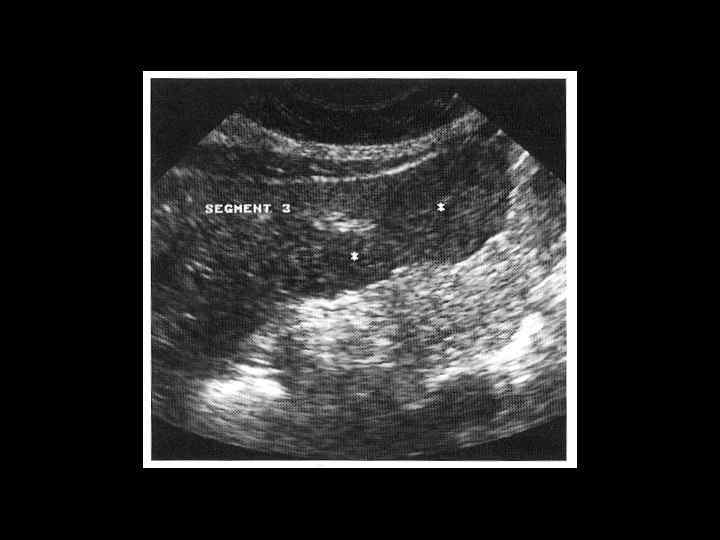

Клиническое наблюдение. Пациентка К, 1966 г. р.

Та же пациентка